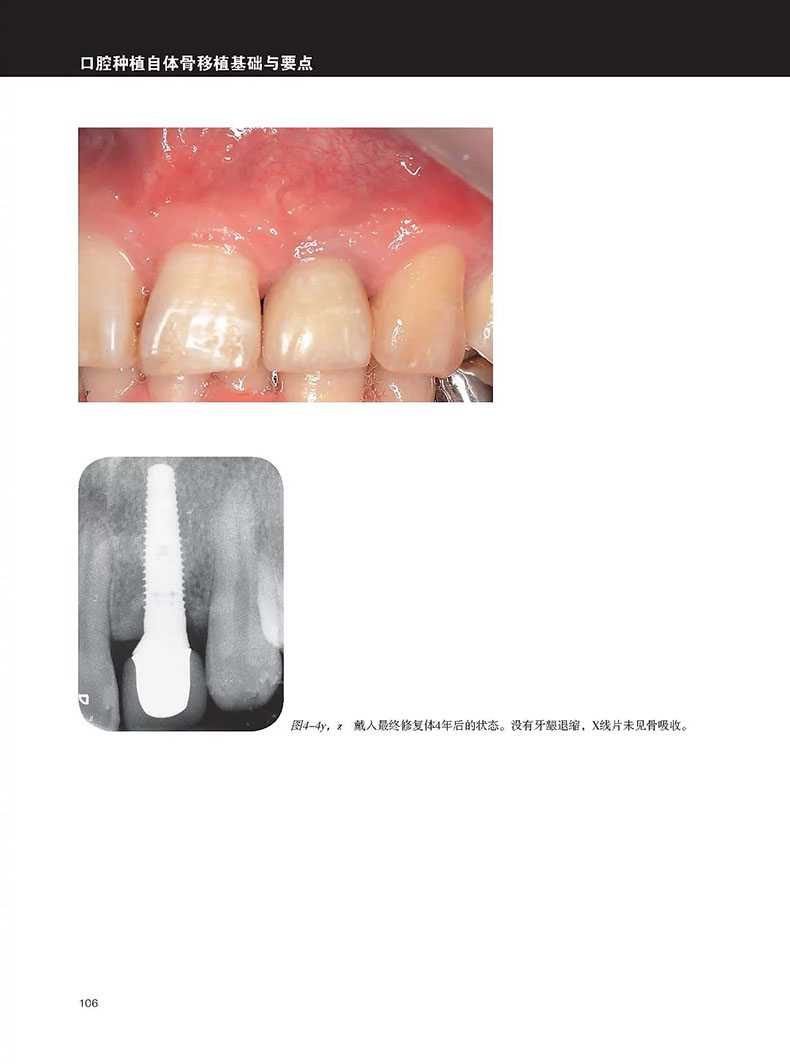

單顆上前牙缺失